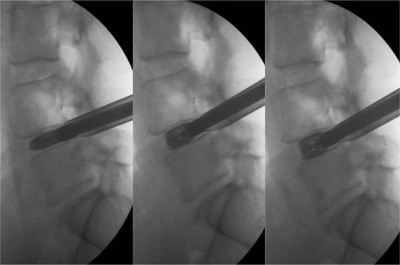

Imatges fluoroscòpies de la inserció de l’implant expansible en un disc col·lapsat i la seva expansió progressiva restaurant l’altura original del disc intervertebral (d’esquerra a dreta)